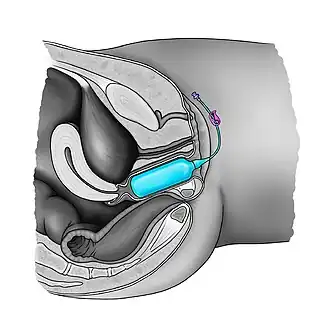

Dilation therapy

Most cases of vaginal hypoplasia associated with CAIS can be corrected using non-surgical pressure dilation methods.[23][25] The elastic nature of vaginal tissue, as demonstrated by its ability to accommodate the differences in size between a tampon, a penis, and a baby's head,[85] make dilation possible even in cases when the vaginal depth is significantly compromised.[23][25] Treatment compliance is thought to be critical to achieve satisfactory results.[21][23][25] Dilation can also be achieved via the Vecchietti procedure, which stretches vaginal tissues into a functional vagina using a traction device that is anchored to the abdominal wall, subperitoneal sutures, and a mold that is placed against the vaginal dimple.[25] Vaginal stretching occurs by increasing the tension on the sutures, which is performed daily.[25] The non-operative pressure dilation method is currently recommended as the first choice, since it is non-invasive, and highly successful.[25] Vaginal dilation should not be performed before puberty.[34]

Neovaginal construction

Many surgical procedures have been developed to create a neovagina, but none of them are ideal.[25] Surgical intervention should only be considered after non-surgical pressure dilation methods have failed to produce a satisfactory result.[25] Neovaginoplasty can be performed using skin grafts, a segment of bowel, ileum, peritoneum, an absorbable adhesion barrier (Intercede, made by Johnson & Johnson),[93][94] buccal mucosa, amnion, dura mater.[25][95][96] or with the support of vaginal stents/expanders.[97][98] Success of such methods should be determined by sexual function, and not just by vaginal length, as has been done in the past.[96] Ileal or cecal segments may be problematic because of a shorter mesentery, which may produce tension on the neovagina, leading to stenosis.[96] The sigmoid neovagina is thought to be self-lubricating, without the excess mucus production associated with segments of small bowel.[96] Vaginoplasty may create scarring at the introitus (the vaginal opening), which requires additional surgery to correct. Vaginal dilators are required postoperatively to prevent vaginal stenosis from scarring.[23][25] Inflatable vaginal stents are placed in the vagina deflated and then gently inflated.[99] Other complications include bladder and bowel injuries.[25] Yearly exams are required as neovaginoplasty carries a risk of carcinoma,[25] although carcinoma of the neovagina is uncommon.[95][96] Neither neovaginoplasty nor vaginal dilation should be performed before puberty.[25][34]